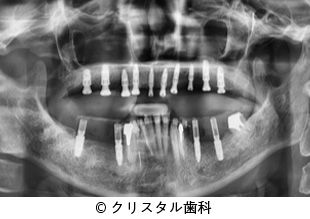

【症例4】すべての歯を失っている上顎にインプラント治療による機能回復をした症例

- すべての歯を失っている上顎にインプラント治療による機能回復をした症例

- 8,540,630円(税込)

- 2年3ヵ月

患者様の症状

長年、上の総入れ歯で苦労していた患者様がインプラント治療を希望されて来院。

治療法

すべての歯を失っていた上の顎と下の奥歯にインプラントを埋入し、セラミックスを被せることで機能的な回復をした。

治療結果

歯のない上の顎にインプラント治療をすることにより、総入れ歯から解放され、以前より審美的にも機能的にも改善した点、患者様からも大きな満足度を得られた感想いただいた。

治療を行う上での注意点 (リスク・副作用)

出血、疼痛、インプラント周囲炎。